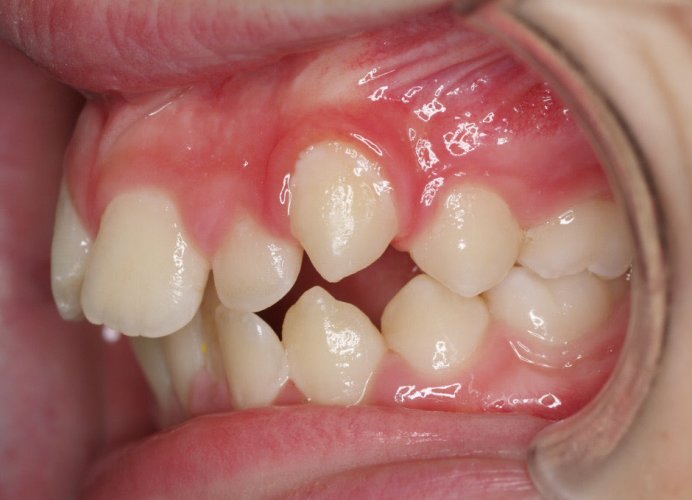

El paciente A.J. de 11 años, acude a nuestra consulta con apiñamiento maxilar importante. El canino lateral (12) está en mordida cruzada. Presenta una Clase II molar y canina, y la línea media está desviada. Se realizó un tratamiento con brackets autoligables metálicos de smartclip 022. La duración del tratamiento fue de 22 meses.

El paciente actualmente ha terminado el tratamiento con brackets y lleva una contención fija de 2-2 en maxilar y 3-3 en mandibular; para complementar también lleva una férula ESSIX durante la noche.

INICIO FINAL